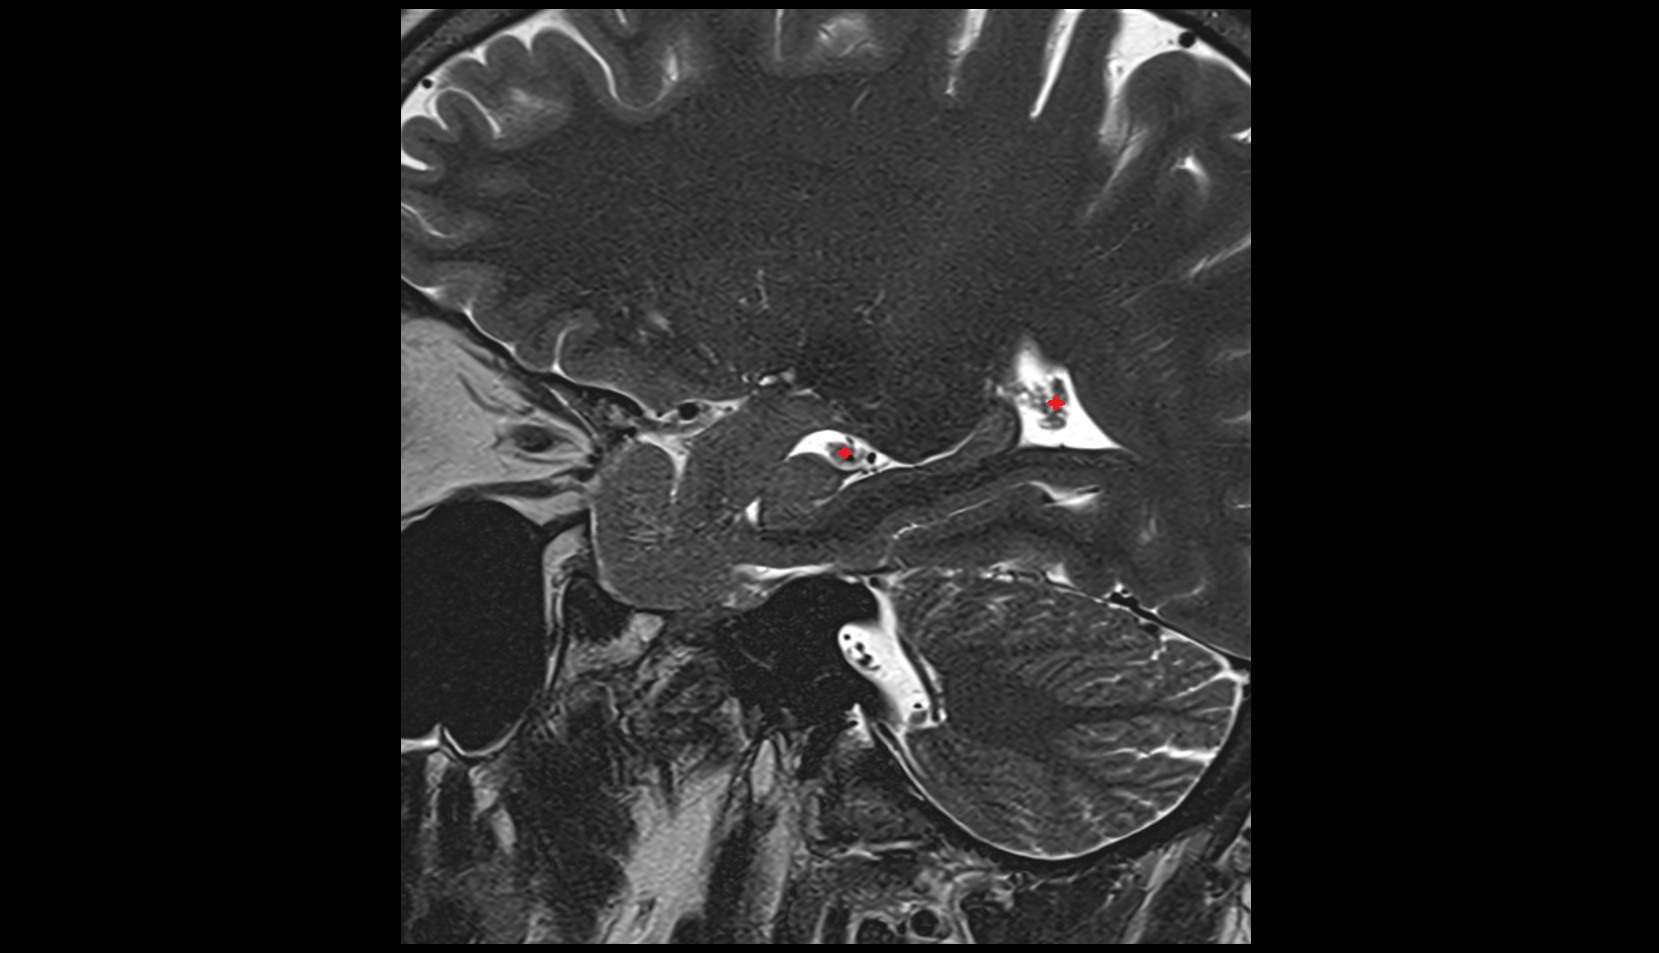

- Body of hippocampus

- Head of hippocampus

- Tail of hippocampus

- Hippocampus